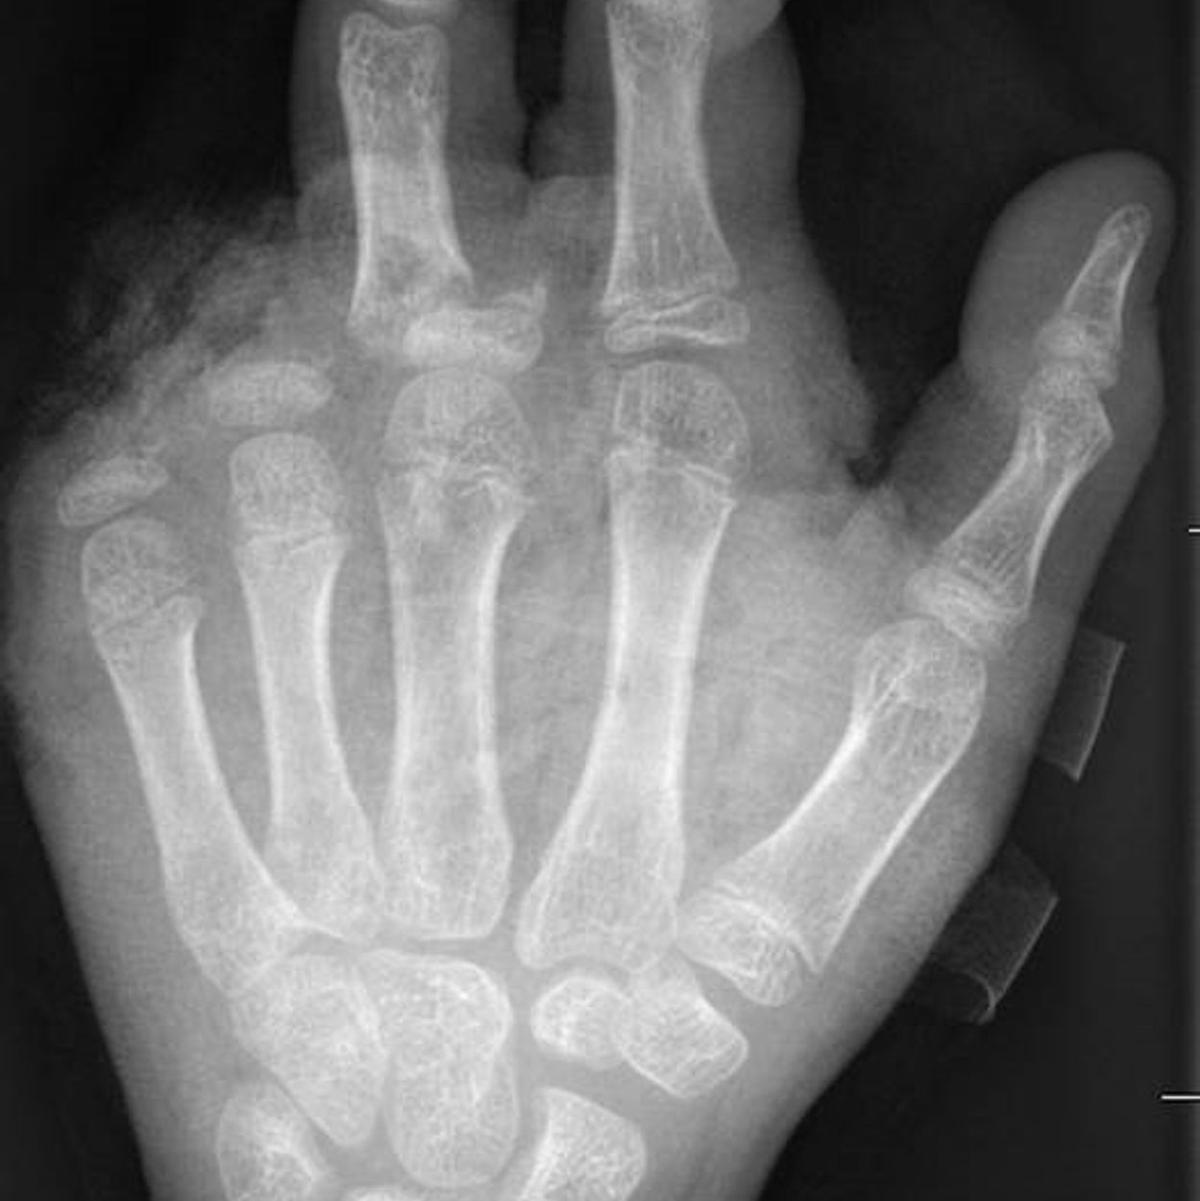

In der Handchirurgie müssten an Silvester im Unfallkrankenhaus rund 20 bis 40 Menschen mit Böllerverletzungen operiert werden, sagt die Ärztin. Dieses Jahr werde sie mir vier weiteren Handchirurgen im Einsatz sein. Die häufigsten Verletzungen entstünden durch explodierende Böller in der Hand.

«Der überwiegende Teil der Verletzungen trägt tatsächlich lebenslange Folgen mit sich, weil die Sprengkraft dazu führt, dass eben nicht nur einzelne Strukturen verletzt sind, sondern immer mehrere. Und das heilt praktisch nie ganz folgenlos ab.» Zum Teil könnten Hände nicht mehr gerettet und müssten amputiert werden.